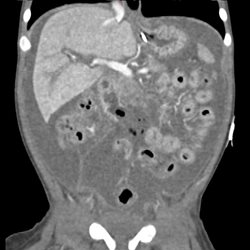

Potential cases of infant abuse. CT.